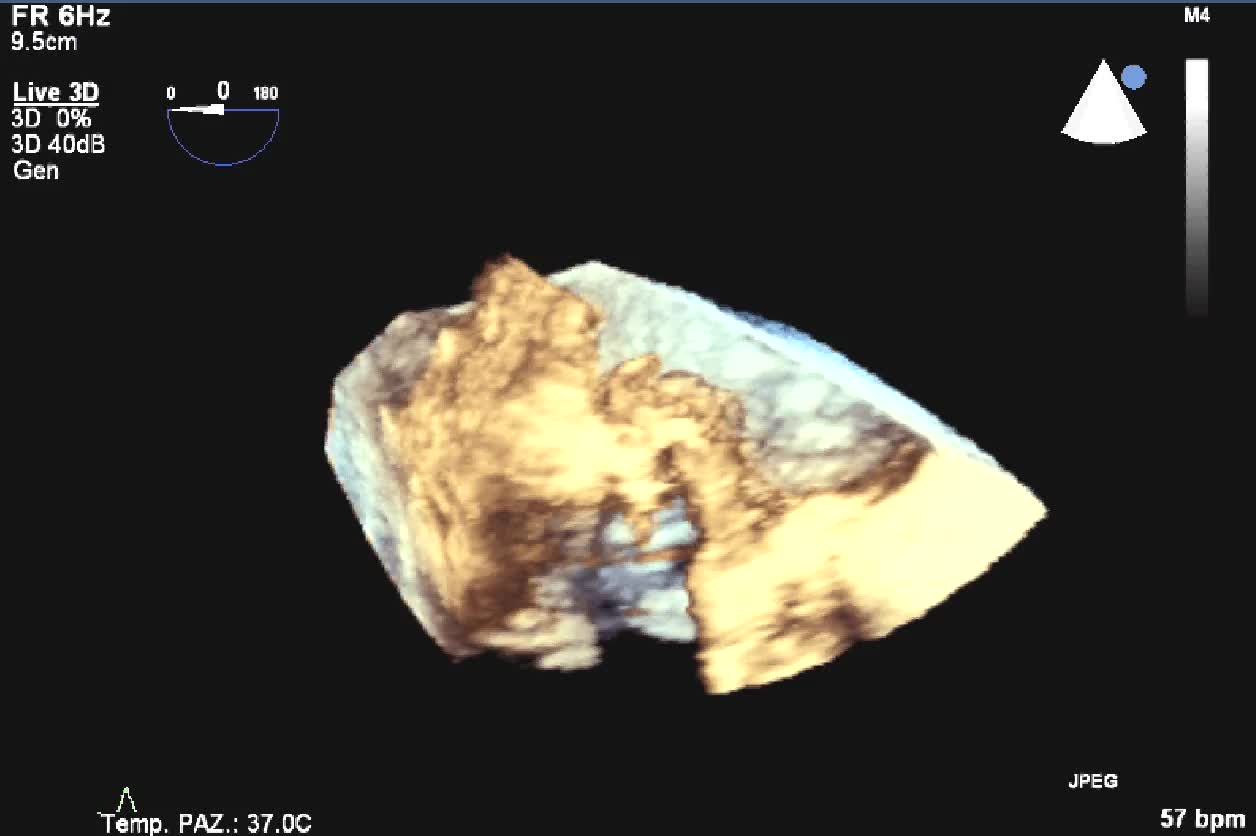

Titolo:

Distacco di protesi meccanica mitralica da endocardite infettiva

Autore:

Manfredo Cerchiello